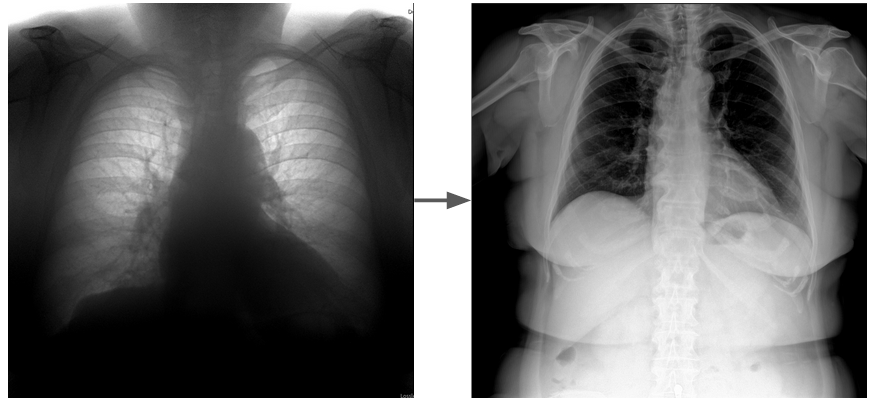

А иногда проблемы возникают не из-за самой ИИ-системы, а из-за изменения свойств входных данных. Распространённый случай - подключение нового оборудования к той же модели.

Слева - типичный вход модели ФЛГ, справа - новичок